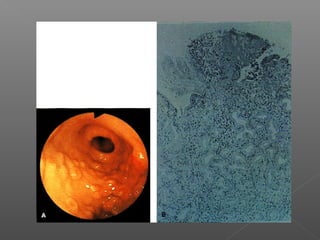

Esclerosis

Ligadura endoscópica de varices esofágicas.

Ligadura

Clasificación de váricesesofágicas Grado I Grado II Grado III Sociedad Japonesa para el estudio de la hipertensión portal.

 Grado 1:cordones que desaparecn con la insuflación.  Grado 2: cordones que se aplanan parcialmente con la insuflación.  Grado 3: ocupan menos del 50% de la luz.  Grado 4: ocupan más de 50% de la luz.

Manejo: Prevención de sangrado: ›betabloqueo › ligadura Tratamiento de sangrado: › Escleroterapia › ligadura › farmacológico Prevención de resangrado: › Endoscópico › farmacológico